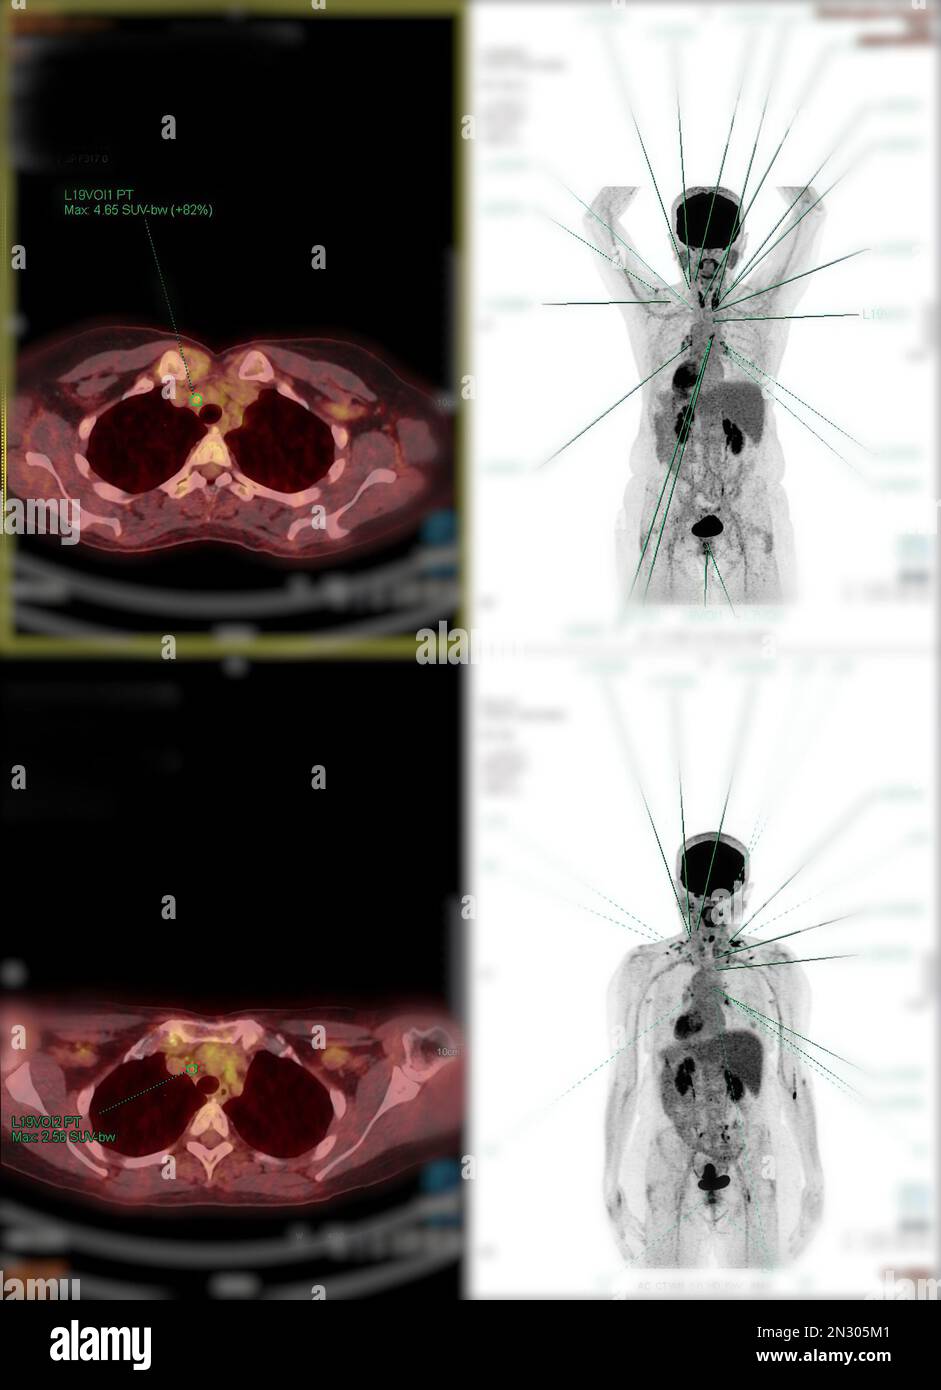

RF2N305M1–La tomographie par émission de positrons (TEP) CT scan utilise un médicament radioactif (traceur) pour montrer l'activité métabolique normale et anormale de tout le corps humain

RF2N305M5–La tomographie par émission de positrons (TEP) CT scan utilise un médicament radioactif (traceur) pour montrer l'activité métabolique normale et anormale de tout le corps humain

RF2N305BY–La tomographie par émission de positrons (TEP) CT scan utilise un médicament radioactif (traceur) pour montrer l'activité métabolique normale et anormale de tout le corps humain